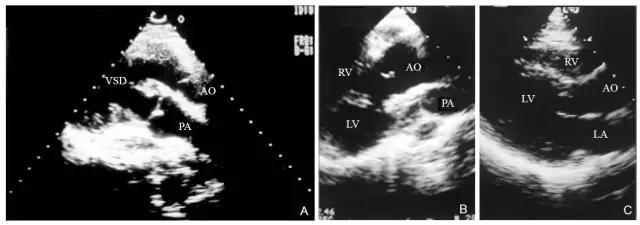

上海医科大学中山医院曾报道一组大动脉转位的超声心动图特征,他们认为在胸骨旁左心室长轴切面上,二维超声心动图可显示两根大动脉在心底部沿其纵轴方向呈前后平行排列关系(图10-4-3),前位的血管内径粗大,与前位的心室相连接;后位的血管内径较细小,与后位的心室相连接。其各自的半月瓣也常在同一高度上得以同时显现,这些表现与正常大动脉根部的超声心动图表现截然不同。

图10-4-3 完全型大动脉转位的胸骨旁左心室长轴切面

图A 为胸骨旁左心室长轴切面显示两根大动脉呈前后平行排列,前位的血管为主动脉,后位的血管为肺动脉,同时存在室间隔缺损;图B 为胸骨旁左心室长轴切面显示肺动脉瓣瓣下狭窄;图C 为正常人胸骨旁左心室长轴切面,其心脏的结构和方位截然不同(AO-主动脉 LA-左心房 LV-左心室PA-肺动脉 RV-右心室 VSD-室间隔缺损)